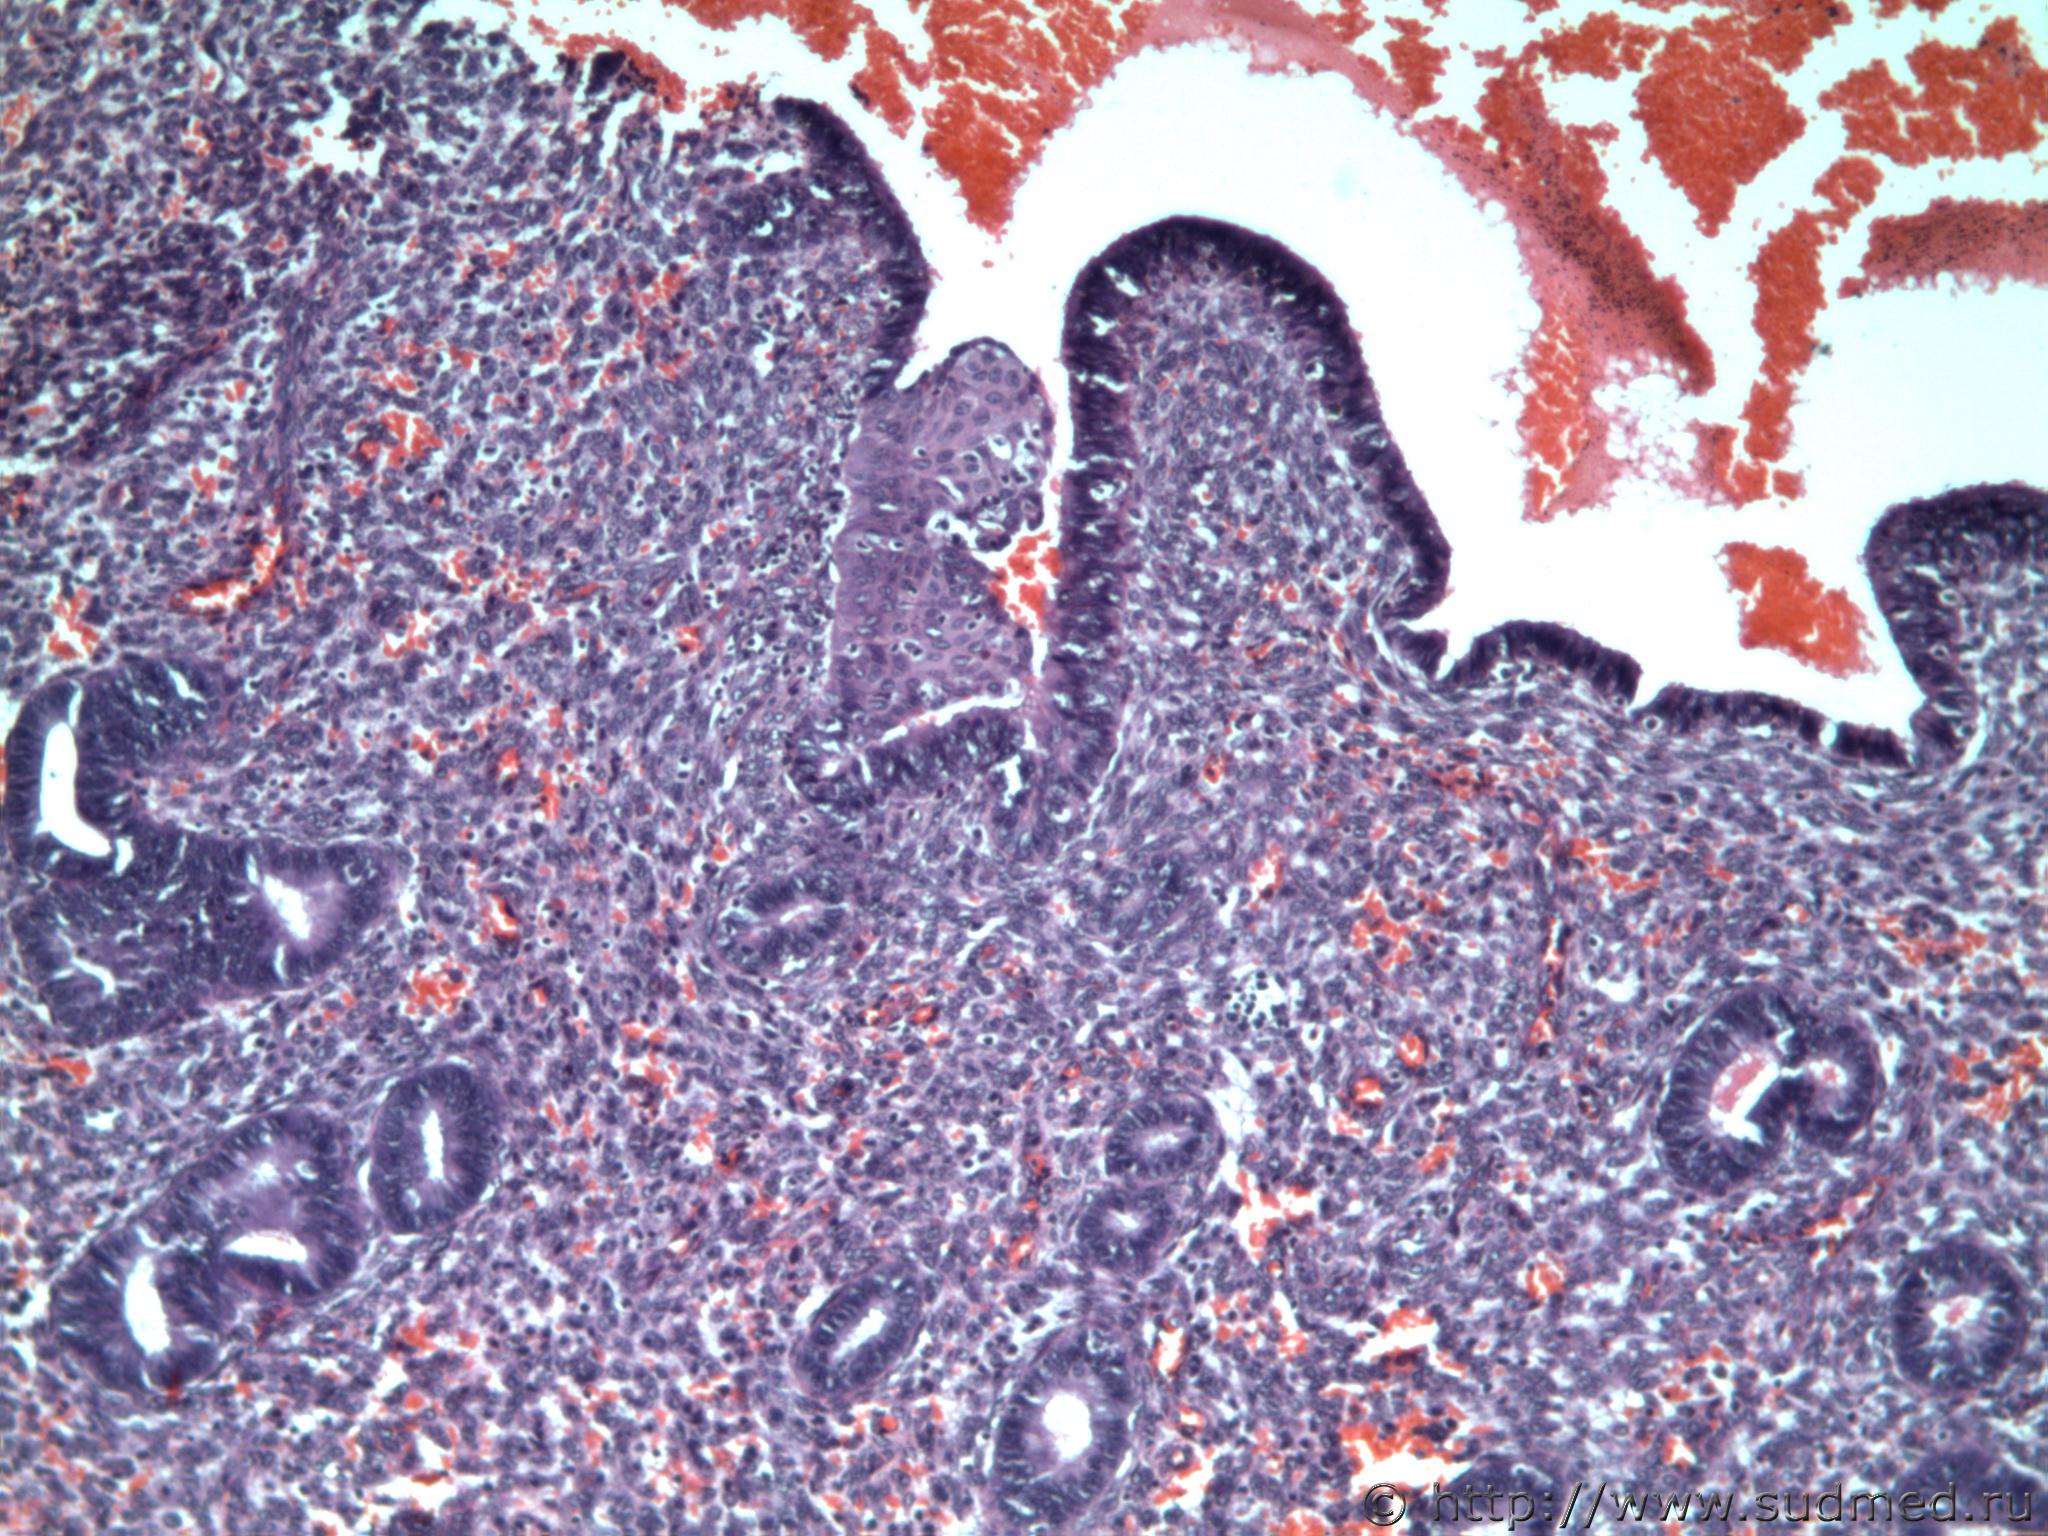

Трубная беременность (внематочная)

Плоскоклеточная метаплазия эндометрии